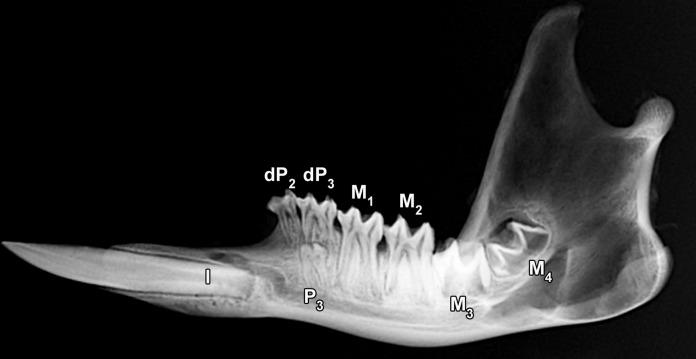

Developmental and Post-Eruptive Defects in Molar Enamel of Free-Ranging Eastern Grey Kangaroos (Macropus giganteus) Exposed to High Environmental Levels of Fluoride.

Dental fluorosis has recently been diagnosed in wild marsupials inhabiting a high-fluoride area in Victoria, Australia. Information on the histopathology of fluorotic marsupial enamel has thus far not been available. This study analyzed the developmental and post-eruptive defects in fluorotic molar enamel of eastern grey kangaroos (Macropus giganteus) from the same high-fluoride area using light microscopy and backscattered electron imaging in the scanning electron microscope. The fluorotic enamel exhibited a brownish to blackish discolouration due to post-eruptive infiltration of stains from the oral cavity and was less resistant to wear than normally mineralized enamel of kangaroos from low-fluoride areas. Developmental defects of enamel included enamel hypoplasia and a pronounced hypomineralization of the outer (sub-surface) enamel underneath a thin rim of well-mineralized surface enamel. While the hypoplastic defects denote a disturbance of ameloblast function during the secretory stage of amelogenesis, the hypomineralization is attributed to an impairment of enamel maturation. In addition to hypoplastic defects, the fluorotic molars also exhibited numerous post-eruptive enamel defects due to the flaking-off of portions of the outer, hypomineralized enamel layer during mastication. The macroscopic and histopathological lesions in fluorotic enamel of M. giganteus match those previously described for placental mammals. It is therefore concluded that there exist no principal differences in the pathogenic mechanisms of dental fluorosis between marsupial and placental mammals. The regular occurrence of hypomineralized, opaque outer enamel in the teeth of M. giganteus and other macropodids must be considered in the differential diagnosis of dental fluorosis in these species.

Molar eruption and identification of the eastern grey kangaroo (Macropus giganteus) at different ages.

J Vet Med Sci. 2018 Apr 18;80(4):648-652. doi: 10.1292/jvms.17-0069. Epub 2018 Feb 15.